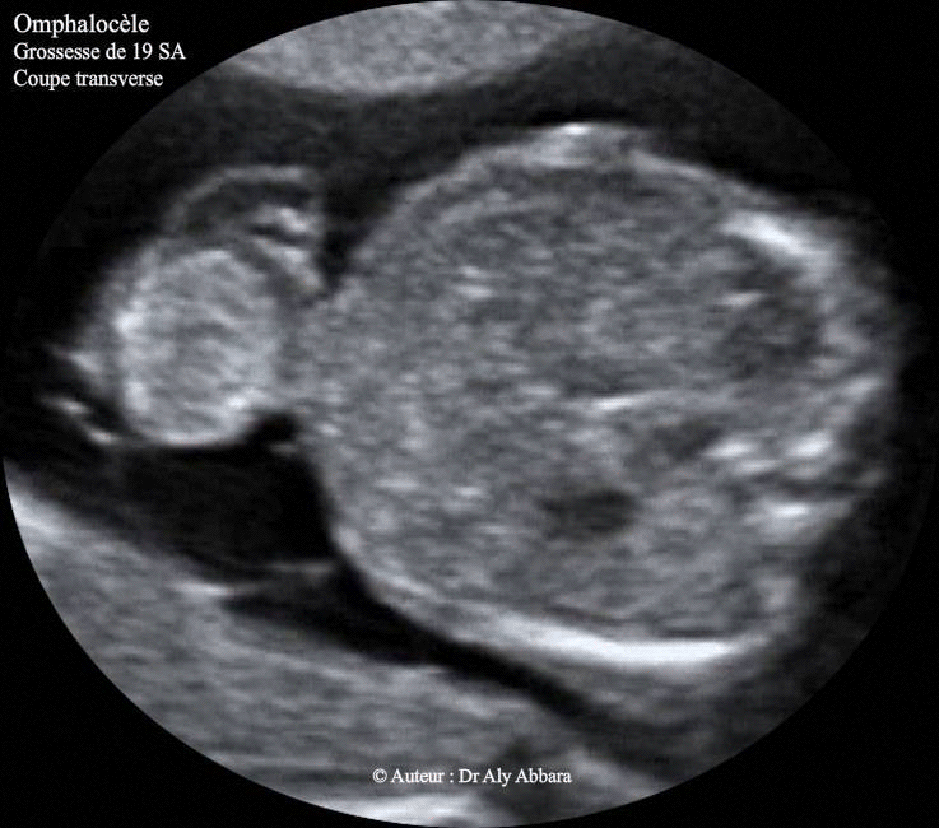

- Images échographiques montrant une grossesse de 19 SA caractérisée par la présence d'une volumineuse omphalocèle contenant une partie des anses grêles et une composante kystique uniloculaire.

Les autres anomalies fœtales associées à cette omphalocèle : un canal atrio-ventriculaire et une bradycardie constante à 80 - 60 bpm ; une fente labiale unilatérale, et enfin, un retard de croissance sévère et harmonieux.

Le caryotype fœtal ne montre pas d'anomalie chromosomique associée (46, XX).